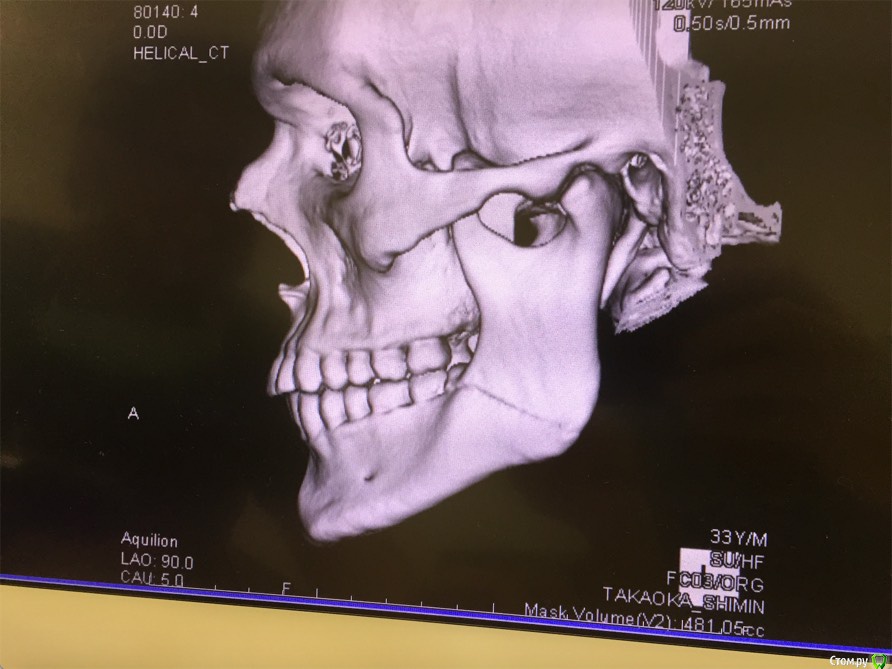

cinovka Опубликовано 10 сентября, 2015 Поделиться Опубликовано 10 сентября, 2015 Здравствуйте. Помогите советом. 15 августа получил перелом нижней челюсти с левой стороны в районе 7-8го зуба.25 числа наложили титановую пластину на место перелома и зашинировали. 3 сентября сняли шины. Разрез делали в ротовой полости и снаружи, для закрутки шурупов.Наружную рану опять вскрыли 1го сентября, т к началось нагноение. Гной выходит постоянно уже 9й день. все болит. зуб мудрости лежит в десне и очень сильно болит.Прошла неделя после снятия шин, а рот также не открылся. максимально открывается на 1-1,2 см.Я нахожусь за границей и врач мой толком ничего не обьясняет.Ответьте пожалуйста на следующие вопросы : 1) Кода пройдет нагноение? И почему оно произошло? (антибиотики, повязки и полоскания постоянные). 2) Когда откроется челюсть? 3) Когда можно будет удалить лежачий зуб мудрости? Снимки номер 1,2,3,4 сделаны до операции 17 августа.Снимки номер 5,6 сделаны сегодня 10 сентября. Заранее спасибо за ответы. Жду с нетерпением. Алексей. Ссылка на комментарий

ПалСаныч Опубликовано 10 сентября, 2015 Поделиться Опубликовано 10 сентября, 2015 С колесниковым не согласен категорически. Полностью поддерживаю криокова. Это не секвестр, это наложение двух линий перелома с внутренней и наружной стороны. Если б ко мне попал пациент с такой проблемой, то я предложил бы ему такую тактику: 1 пластины снять нафиг, потому чо они там не работают, ибо наложены стнарушением правил остеосинтеза, а так же потому что в ране гной; 2 во время снятия пластин через разрез задренировать рану и провести антибактериальную терапию; 3 наложить опять шины если есть подвижность отломков после снятия пластин. 4 зуб убрать вместе с пластинами. Все написанное ИМХО. 6 1 Ссылка на комментарий

Maxfac Опубликовано 11 сентября, 2015 Поделиться Опубликовано 11 сентября, 2015 + к ПалСанычу. Зуб бы удалил первым этапом, затем - пластины. Я бы еще добавил тщательную ревизию через наружный доступ: что-то симптоматика какая-то подозрительная. Надо наркотизировать, имхо. Ссылка на комментарий

kriokov Опубликовано 11 сентября, 2015 Поделиться Опубликовано 11 сентября, 2015 1. По Вашим жалобам и клинике тянет на остеомиелит, точно только очно можно2. Вам сделали оптг, аппарат ходил кругом как Вы выразились. При таком снимке, да и при выполнении снимков другими методами линий перелома кажется что две, на самом деле плоскость перелома одна (ПалСаныч выше описал)3.учитывая, что гноетечение и со стороны полости рта в обл 8 и снаружи из послеоперационной раны и отек лица держится выраженный я бы члх еще раз потревожил, не решите на месте, надо возвращаться. Имхо Ссылка на комментарий